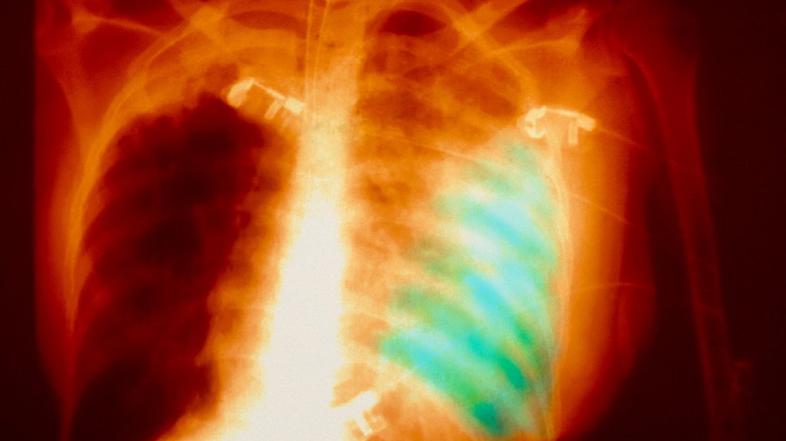

Pljučnica Profimedias